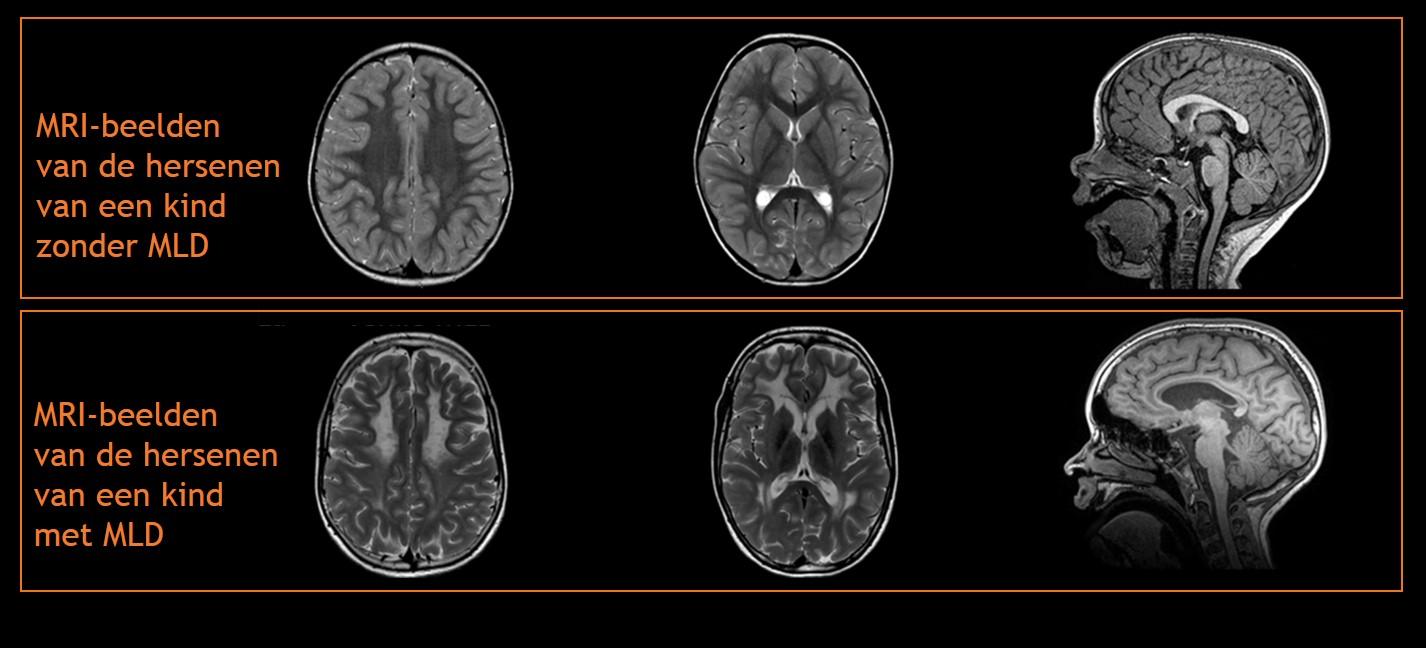

Op de MRI-afbeeldingen kan de neuroloog afwijkingen in de witte stof zien die goed passen bij de ziekte MLD. In de beginfase van de ziekte, als er nog geen of weinig ziekteverschijnselen zijn, kunnen deze afwijkingen nog afwezig of slechts heel subtiel zijn. Naar mate de ziekte zich vordert, breiden de afwijkingen zich uit op meerdere plekken in de hersenen. Hieronder ziet u een aantal MRI-afbeeldingen van de hersenen van een kind zonder MLD en van de hersenen van een kind met MLD. De MRI-afbeeldingen van het tweede kind zijn vijf jaar na het ontstaan van de eerste ziekteverschijnselen gemaakt.